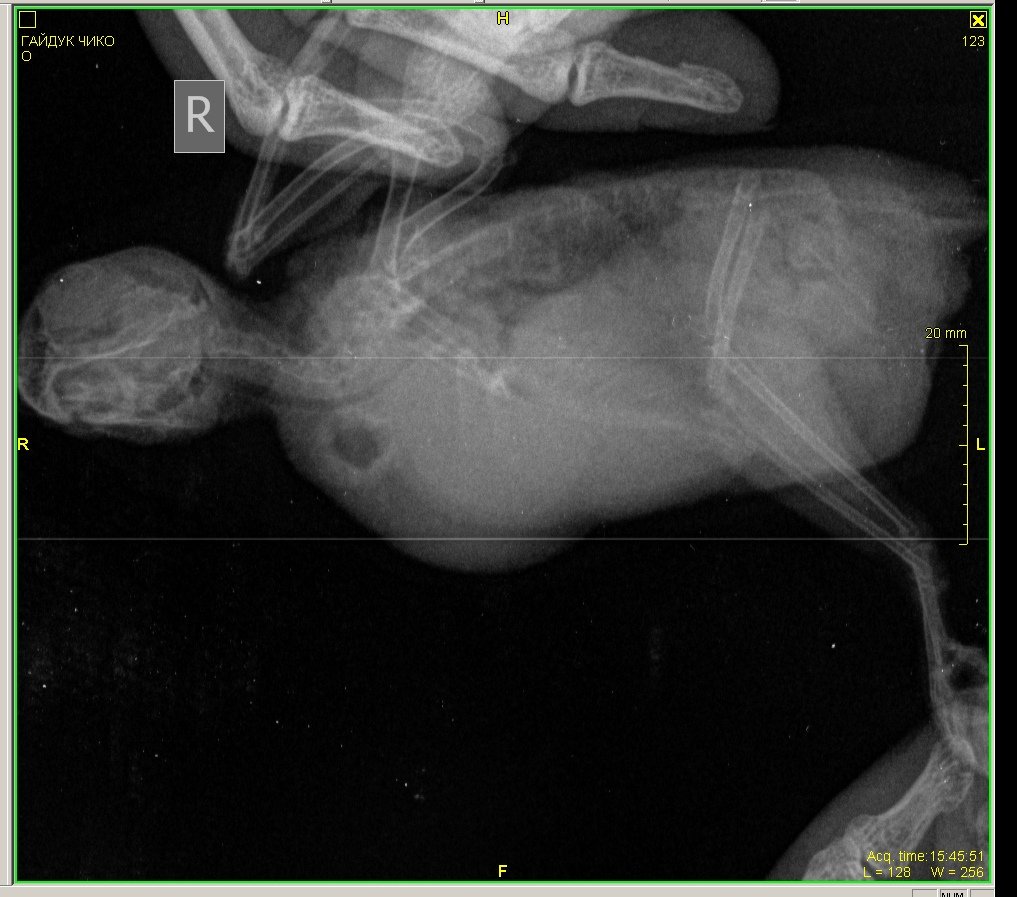

Здравствуйте, корелла самка , возраст 1 год 1 месяц. Вес 100 гр. Поведение - активная , ест, пьет. Оперение нормальное. Питание - овощи, фрукты даю, но практически не ест, каша без молочная детская, чумиза, есть копошилка, сепия, минеральный камень, скелетин с серой, бентонит кормовой, Рио для средних попугаев. Уф лампа есть , световой день 12-13 часов. Весь день летает. Взята была девочка у заводчика в возрасте 3 месяцев, заводчик настойчиво рекомендовала давать песок Рио и рисовую кашу и гречку с желтком яйца, что я и делала 4 раза в неделю, потом я выяснила, что это давать нельзя, и сразу же все убрала и не даю уже около месяца. Первые подозрения на плохое самочувствие были на постоянные вытягивания шеи, иногда трясет головой, умывается очень часто, делая при этом нервные движения при очистке Перьев. Самый основной симптом жидкий помет практически всегда. 12 августа она снесла яйцо ночью, утром я сразу же его выкинула и отвезла к орнитологу. При осмотре орнитологом она сказала , что деформированы носовые ходы , ожирение. Рекомендован был рентген, по рентгену орнитолог сказала , что к попугая : Аэросаккулит(воспаление воздушных мешков), пневмония, нефрит, гепатомегалия, повышенная плотность костей связана с гиперестрогенизмом Были сданы анализы , пока еще не готовы , один готов , вот результат: Цвет: светло-зеленый Консистенция: жидкий Соотношение микроорганизмов: подвижные кокки 50%, палочки 50%, стрептококки Кристаллы мочевой кислоты в большом количестве Нейтральный жир умеренно Билирубин отсутствует Жирные кислоты отсутствуют Соли жирных кислот отсутствуют Крахмал внеклеточный в большом количестве Крахмал внутриклеточный отсутствует Лейкоциты более 10 в поле зрения Эритроциты более 20 в поле зрения Эпителий клоаки в большом количестве Эпителий кишечный в большом количестве Слизь присутствует Дрожжи в большом количестве Простейшие не обнаружено было назначено лечение: Амоксиклав/ Флемоклав/ Экоклав (250 мг) - 1 таблетку растворить в 3 мл воды, давать / 0.2 мл, каждые 12 часов в течение месяца. Целекоксиб (200 мг) 1 капсулу растворить в 10 мл воды, давать по 0.05 мл в клюв 1 раз сутки в течение 14 дней Тербинафин таблетки 250 мг - 1 таблетку растворить в 5 мл воды, давать по 0.03 мл 1 ра в 24 часа в течение месяца. Кальций глюконат 100 мг/мл по 2-3 мл в поилку на 50 мл воды 15 дней. Гептрал/Самеликс в обычной аптеке 400 мг/5 мл по 0.1 мл в день месяц Если здесь есть орнитологи, прошу помогите пожалуйста, я была на консультации 3 врачей, я боюсь давать своей птичке Амоксиклав и тербинафин целый месяц. Не много ли это ? Как вы считаете ? И пожалуйста посмотрите рентген умоляю, скажи , что вы видите ? Насколько плохой анализ помета ? И насколько серьезны поставленные диагнозы? И возможно ли это вылечить? Остальные анализы как придут, я приложу фотографии.

Здравствуйте, нужна помощь! Попугай волнистый, Чико. Возраст - 1,9 3 июня начал без остановки чесать попу, выдергивать перья сзади, вести себя беспокойно. 4 июня отвезла к врачу-орнитологу Полозу, взял мазок из зоба и посмотрел кал под микроскопом - определил Гельминтоз, выписал метронидазол 10 дн, решила показать др врачу - Грязнову. 5 июня - отвезла, глянул в микроскоп калл - сказал, что "единичные случаи паразитов", добавил к лечению Нистатин, посоветовал рентген, сделала рентген, но врачам из Минска не показывала , тем,у которых была на приеме, показала знакомому ветеринару -Валерии Сороке, на ее взгляд возможны проблемы с легкими, вчера заметила, что Чико чихнул мокрым! Также сейчас у него зеленый помет, возможно от метронидазола. Совсем я в рестерянности, продолжать лечить глистов? или лечить легкие? Валерия прописала следующие препараты:1. амоксиклав 125 мг 0.2 мл 2 раза в день 14 дней ( 1/2 табл растворить в 2 мл воды) 2. флуканазол 50 мг внутрь 1/10 капс 1 раз в день 14 дней 3. метронидазол 4. иммунофан Помогите поставить точный диагноз по снимку, у нас как таковых орнитологов нет... Сейчас поведение птицы: веселый, активный, кушает хорошо, чешется, чешет попу, чихи мокрые редко.

г.Новодвинск. Специалистов нет. Проблема: плохо ходит, падает, не ест. Помет изменился. Предположение: застревания яйца Попугай корелла самка 6 лет. Клеточное содержание. Практически без выпуска из-за собаки,детей.Неслась практически ежегодно. Корм только РИО для средних попугаев, не ограничено. Съедала много.Пила воды много. Овощи, зелень, мин.подкормка,сепии и т.п. в рационе отсутствовали. На окне в клетке в комнате. Проблемы начались в начале недели, после того как снесла яйцо. Упала с жердочки, и практически перестала ходить. Обратились к девушке волонтеру по птицам. Единственному человеку который хоть как то попытался помочь и отправил сюда. Рекомендовано: Рентген(сделан), анализы( бак.посев,копрограмма) НЕ ДЕЛАЮТ в гор.вет.лаб. Обратиться к специалисту(поэтому тут). Улучшить условия кормления и содержания(делаем). Помогите спасти птицу,пожалуйста.Ошибки осознали..исправим,но очень нужна помощь. Назначено: вазелиновое масло 0,4мл в клоаку, 0,1мл в клюв 1 раз в сутки. . Водяная баня. Кормление насильно через шприц запаренной крупой с яблочным пюре детским. Глюконат кальция ампульный по 0,05мл 1 раз в сутки, клюв. Мильгамма 1/8 таблетки в клюв. Энтеросгель 0,1мл в разведении 1:1 с водой. Нужна помощь в лечении(